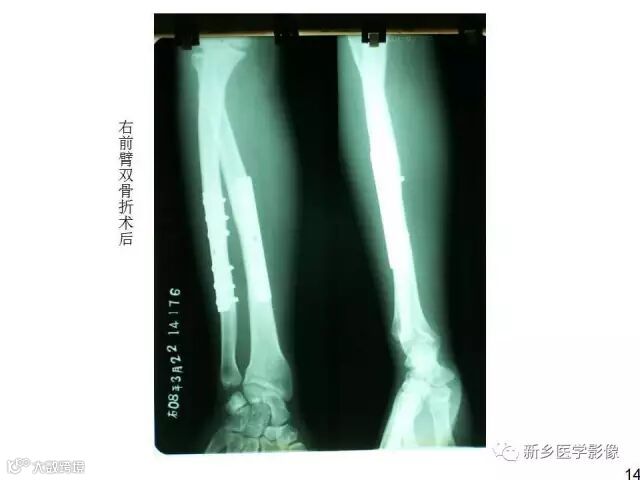

全身常见骨折X线汇总

来源丨

新乡

医学影像